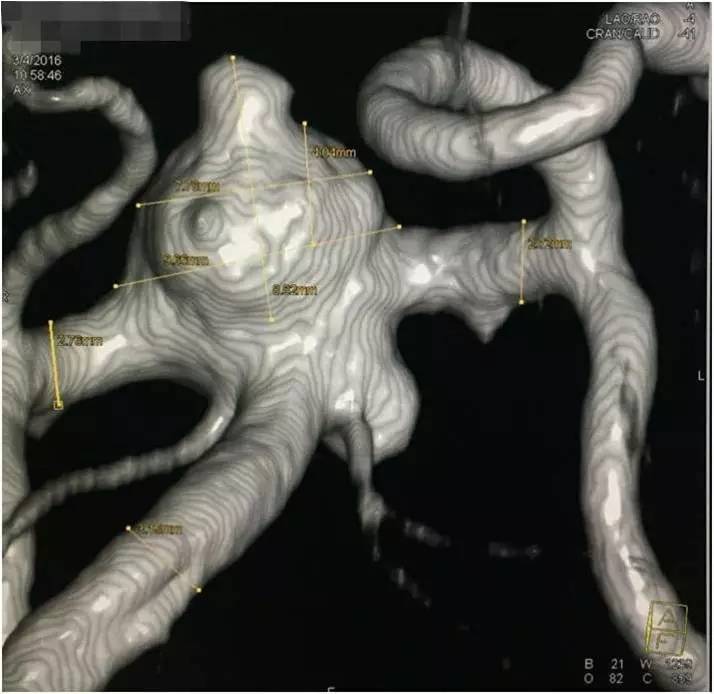

▼基底动脉顶端动脉瘤和载瘤动脉测量